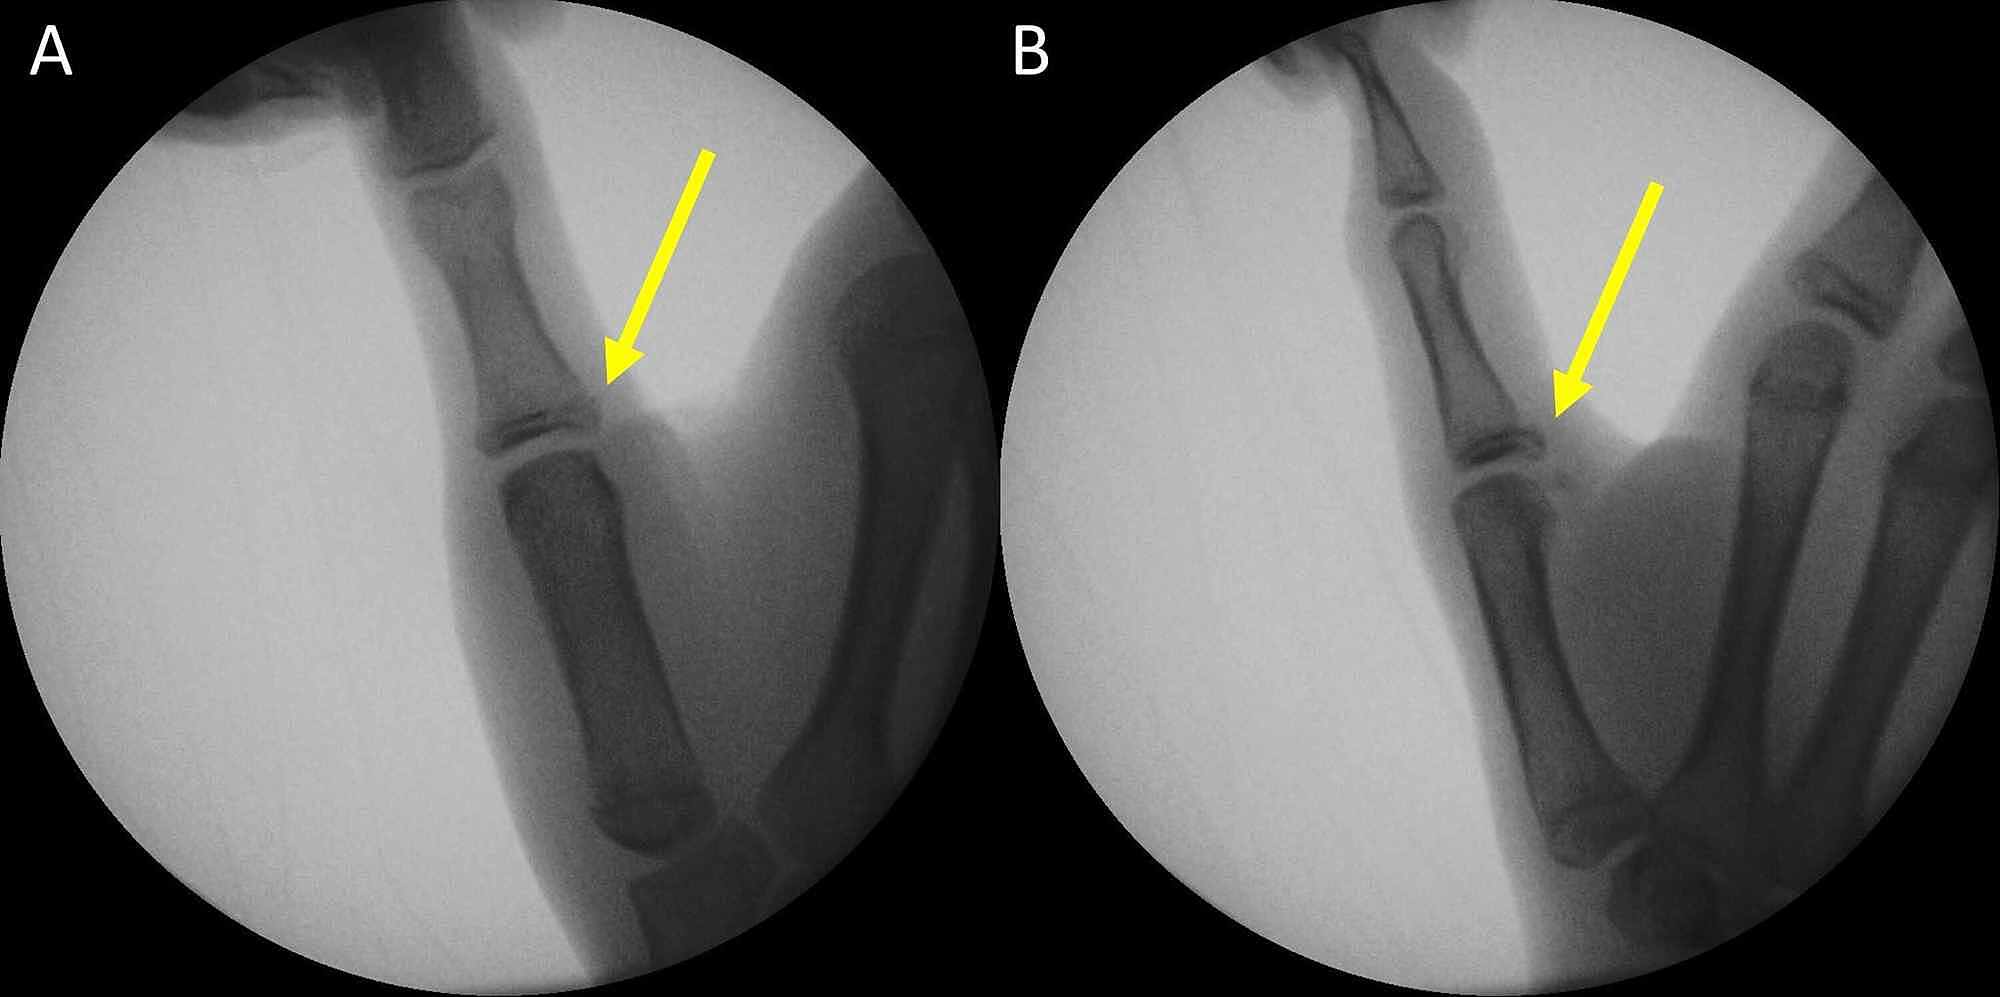

Avulsion Fracture And Ligament Damage Of The Right Thumb With 318

Avulsion Fracture And Ligament Damage Of The Right Thumb With 318 Avulsion Fracture Sports Med They are typically diagnosed with a. avulsion fractures of the ischial tuberosity are the most common hip avulsion fracture (3). — in this article we present 3 clinical cases of patients with indirect trauma, such as the anterior fracture of. Your bones are connected to each other through ligaments and connected to your. — an avulsion fracture. Avulsion Fracture Sports Med.